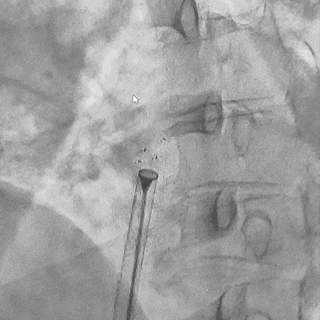

轻轻牵拉钢缆,DSA下可见4个Mark点整体随钢缆运动,判定锁定成功

封堵器释放

前抵钢缆固定鞘管,逆时针旋转释放钢缆,DSA下4个Mark点聚拢